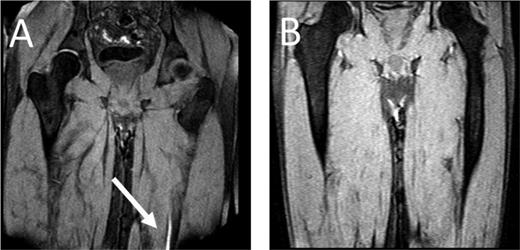

MRDTI of patient from case. (A) The white arrow indicates the fresh thrombus in the popliteal vein of the right leg. For contrast, B depicts the MRDTI of a patient with residual thrombosis in the left popliteal and femoral vein: no DTI signal is present.

As for our patient, his Wells score for DVT indicated “likely probability” (total of 2 points, 1 point for “calf enlargement >3 cm compared with the other site” and 1 point for “pitting edema”), indicating that a D-dimer test could definitely not be used for ruling out DVT.6,20 Because the patient fulfilled all inclusion and none of the exclusion criteria for the Theia study, he was referred for MRDTI, which showed a clear signal in the right popliteal vein (Figure 1), confirming the diagnosis of recurrent ipsilateral DVT. After 6 months of treatment, a reference CUS was performed and showed persistent incompressibility of the right popliteal vein.